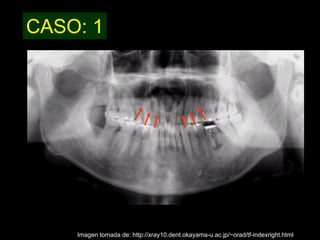

El quiste nasopalatino es un quiste embrionario situado en la línea media en la parte anterior del paladar, que se origina de los restos del conducto nasopalatino. Generalmente aparece entre los 40-60 años y se presenta como un aumento de volumen blando y no doloroso entre los incisivos centrales superiores que puede causar divergencia radicular. Las características radiográficas incluyen una lesión radiolúcida, bien delimitada y de forma redondeada u ovalada que cruza la línea media maxilar.